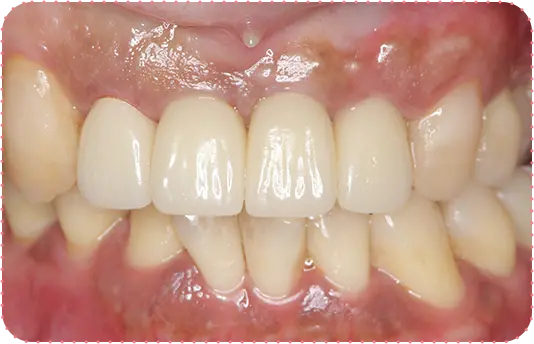

Before

After

主訴

歯がボロボロで気になる、短い歯をどうにかしたい

治療期間

1年

治療費

150万円

治療内容

歯肉整形術、右上1~5番と左上1~5番をセラミッククラウンにて修復

治療のリスク

咬み合わせによっては、セラミックが欠ける可能性があります。